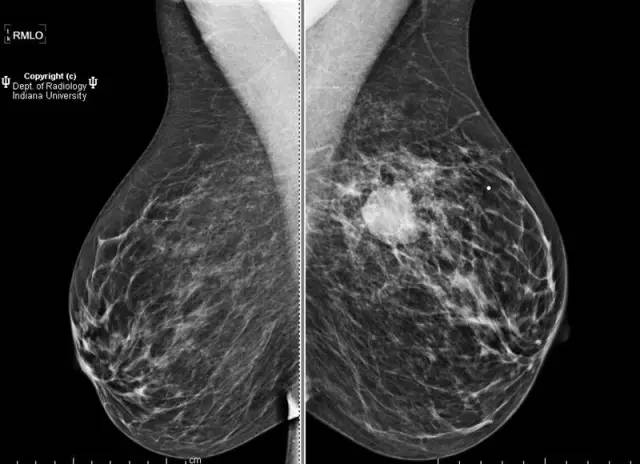

乳腺钼靶左乳腺内上象限见3.1cm卵圆形等密度肿块,部分界限清晰。超声见一2.5 x 2.1 x 1.9 cm混合回声肿块,宽大于高,边界清晰,后部回声增强。

浸润性导管癌

Invasive ductalcarcinoma